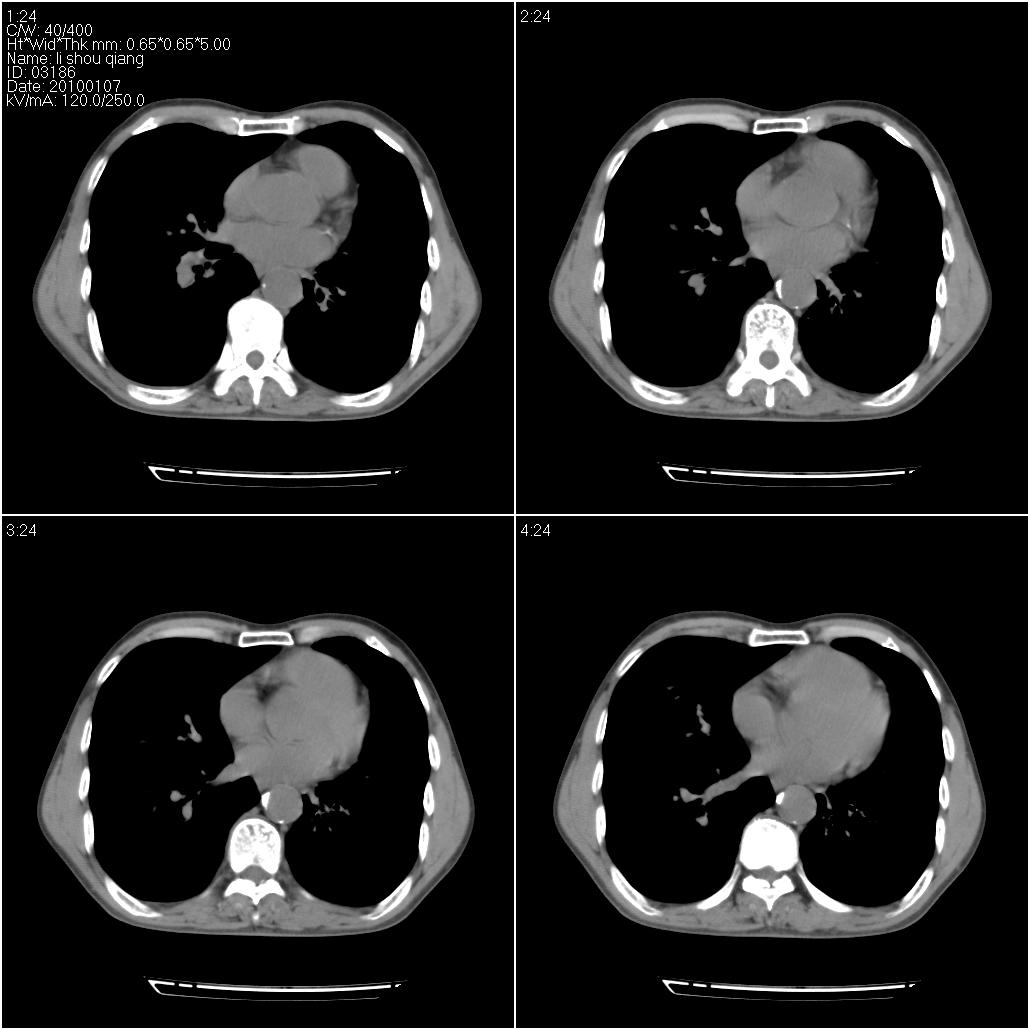

标题: CT24038:男性,58岁。主因咳嗽带血性CT检查。 [打印本页]

标题: CT24038:男性,58岁。主因咳嗽带血性CT检查。

右肺中叶外侧段可见团块影,外形不规则,内见空泡征。左下肺见蜂窝状低密度透亮影,部分层面主动脉旁瘤样突出。考虑右肺中叶外围型肺癌可能性大,左下肺支气管扩张,主动脉弓瘤样突出。

考虑右肺癌可能性大,左下肺支气管扩张,主动脉弓瘤样突出?建议增强

1)考虑右肺中叶周围型肺癌并癌性空洞形成。2)左肺下叶支气管扩张可能性大。

右肺中叶外侧段见一不规则的软组织肿块,边缘可见毛刺,并见厚壁空洞,与胸膜分界欠清。另左下肺见多个小囊状扩张区

1、右肺中叶周围型肺癌(内空泡)。

2、左肺下叶支扩,不除外合并肺囊肿。

3、建议冠状位重建除外主动脉弓息室样动脉瘤。